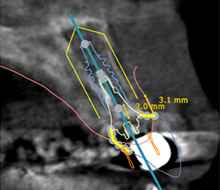

②計画通りのインプラント埋入

補綴物を考慮した理想的な埋入位置

精密な計算を手術に反映できる

ガイド手術を行うとインプラントを安全に正確に埋入することが可能で、造骨が必要な例でも低侵襲で、ストレスを最小限にすることが可能な場合もあります。